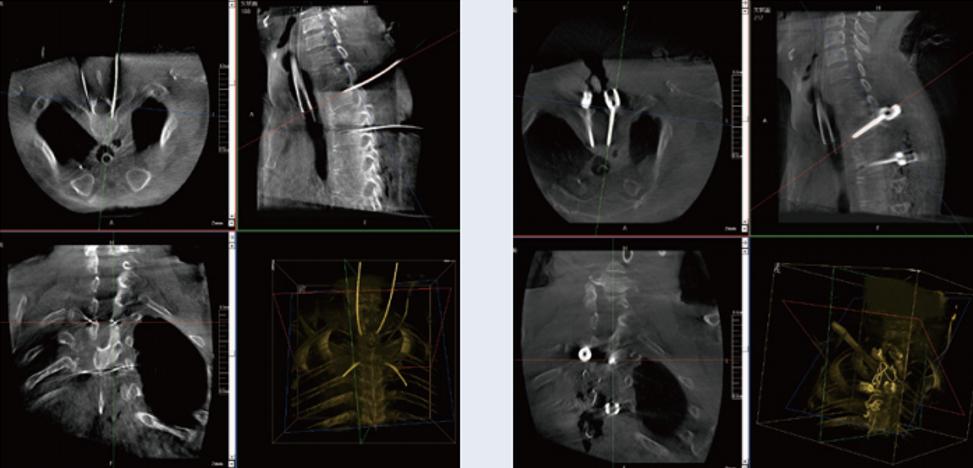

螺釘規(guī)劃后的圖像

植入螺釘后的圖像

術(shù)中三維C形臂與脊柱導(dǎo)航機(jī)器人配合應(yīng)用,實(shí)現(xiàn)準(zhǔn)確定位,確保了手術(shù)安全、高效完成。術(shù)后二維、三維影像顯示手術(shù)效果良好,達(dá)到預(yù)期目的。

普愛醫(yī)療三維C形臂提供了高質(zhì)量的術(shù)中實(shí)時(shí)三維圖像數(shù)據(jù),保障了脊柱導(dǎo)航機(jī)器人手術(shù)的準(zhǔn)確度和安全性,取得不錯(cuò)的手術(shù)效果。同時(shí),術(shù)中三維C形臂特有的斷層成像,能幫助醫(yī)生在術(shù)中非常直觀地判斷螺釘植入的準(zhǔn)確度。